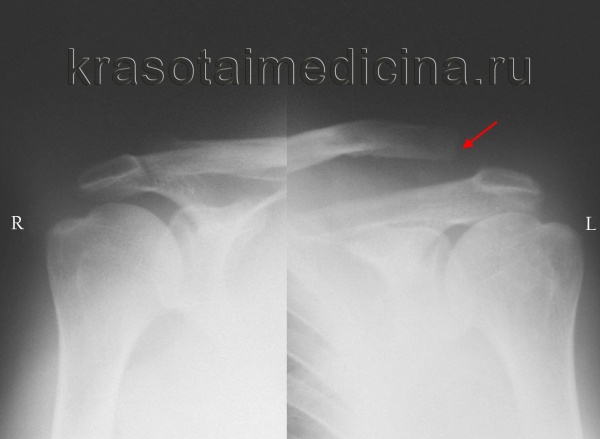

- Рентгенологическое исследование. Для подтверждения выполняют снимок акромиально-ключичного сустава или рентгенографию грудино-ключичного сочленения. При неполных вывихах ключицы в некоторых случаях требуется сравнительная рентгенограмма обеих сочленений, иногда – с функциональной нагрузкой (пациент берет в руки небольшой груз).

Рентгенография акромиально-ключичных суставов. Вывих акромиального конца левой ключицы (справа норма для сравнения).